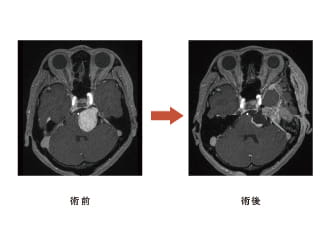

神経鞘腫(しょうしゅ)

38歳女性、左三叉神経鞘腫、外科治療のみ